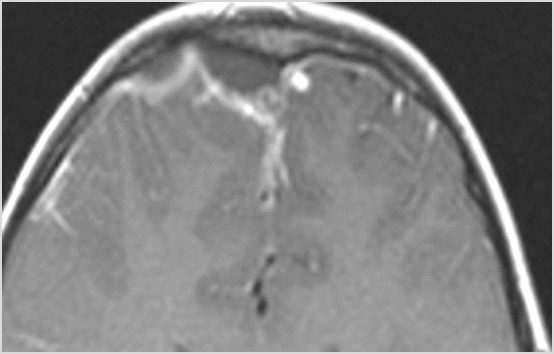

There is evidence of thrombus, thrombophlebitis or other occlusive or inflammatory process of the cortical veins, sphenoparietal sinus or sagittal sinus. [Yes/No]

There is evidence of thrombus, thrombophlebitis or other occlusive or inflammatory process of the cavernous sinus. [Yes/No]